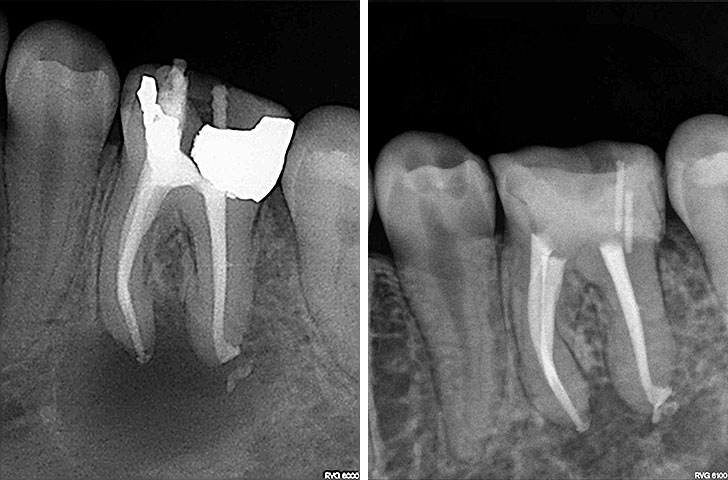

Endodoncija